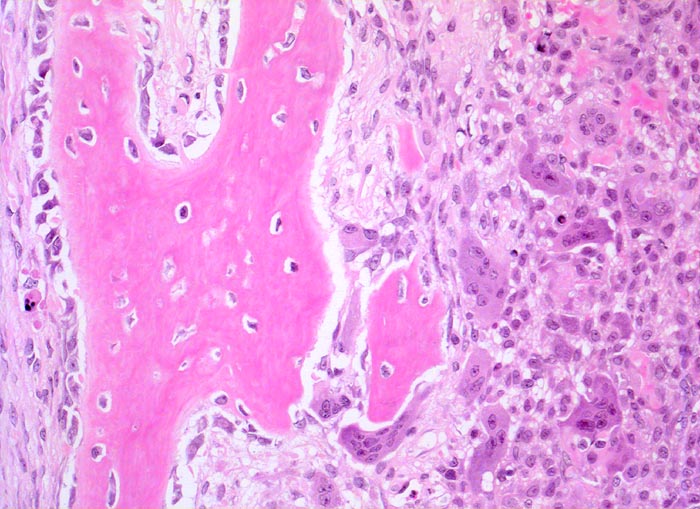

PathoPic – image database / PathoPic ID 4786 - aneurysmatische Knochenzyste (AKZ)

aneurysmatische Knochenzyste (AKZ)

Knochen, Fibula

Beschreibung

Klinik

Lokalisierte Schmerzen und Schwellung in der proximalen Fibula. Im Röntgenbild ist eine Osteolyse erkennbar, die die betroffene Fibula auftreibt. Die Cortikalis über der Osteolyse ist hauchdünn.

Histologie

200

16